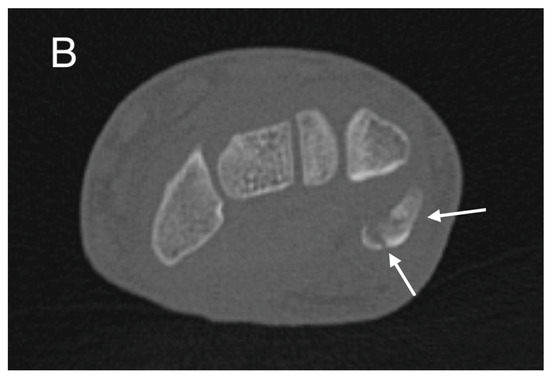

Initial conventional radiographic assessment showed no definitive fracture, with a potential suspicion of a proximal radius fracture (Figure 1). Due to significant tenderness over the radial fossa and pisiform, a CT scan was performed, confirming a nondisplaced scaphoid fracture and a suspected pisiform fracture with dislocation (Figure 2).

Figure 2.

Initial CT study with sagittal (A) and axial (B) images showing a non-displaced fracture of the pisiform bone (white arrows).